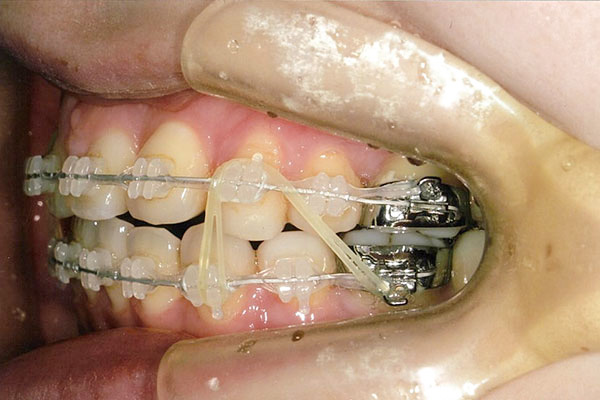

2年1ヶ月後